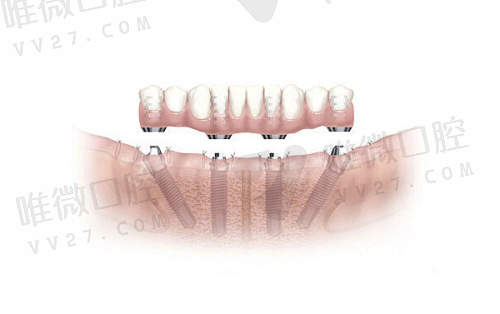

难度较高的情况下,如半口修复、全口重建所用的All-on-4、All-on-6技术,价格则如下:

- 半口(4-6颗种植体支持固定式)价格约:1.5万~3万起

- All-on-4方式半口重建价格:约5万元起

- All-on-6方式半口重建价格:约6万元起

- 全口即刻修复All-on-4方案:约10万元起

- 全口All-on-6:12万元及以上